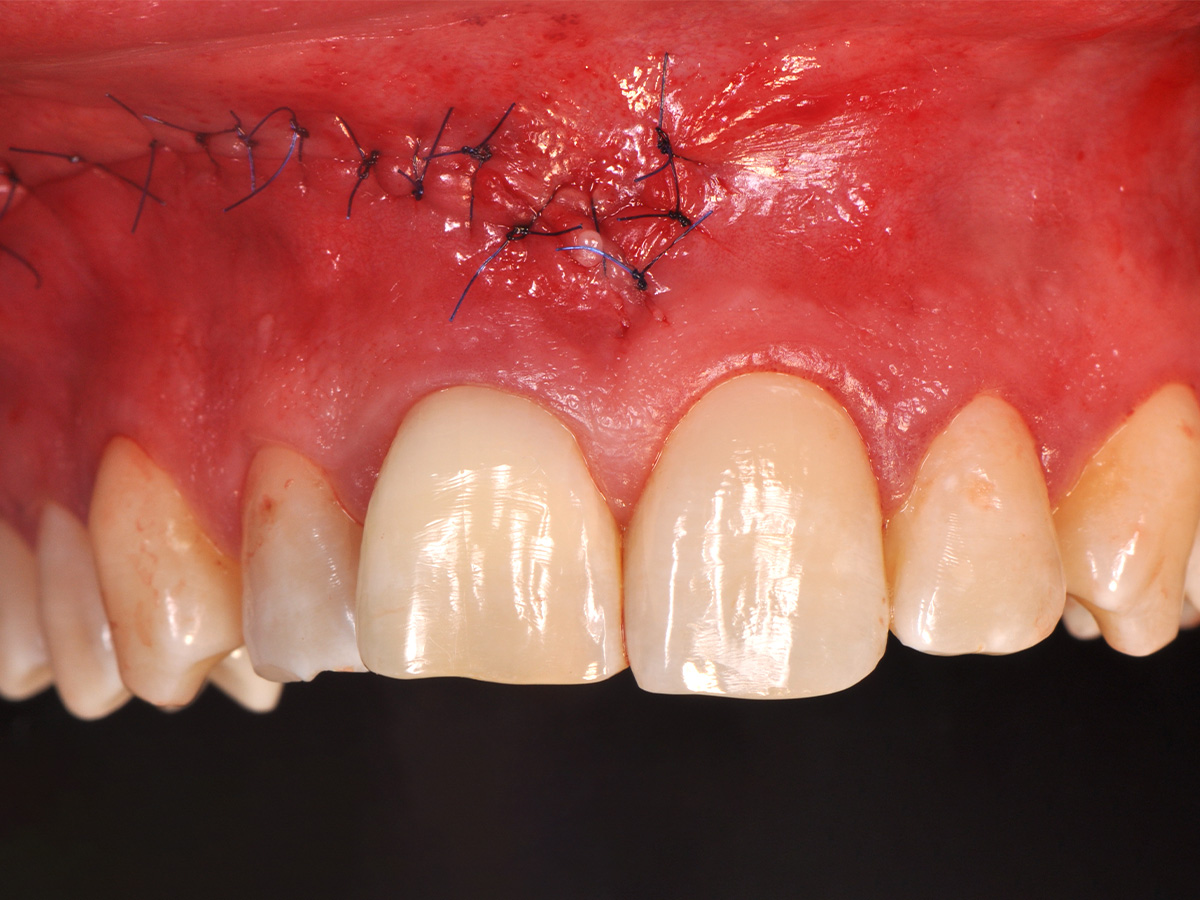

Abbildung 15

Der Wundverschluss erfolgte einschichtig mit nicht resorbierbarem Nahtmaterial (Seralene® 5-0 DS-15).

Mit der Patientin wurde der Versuch des Zahnerhaltes trotz ausgedehnter Zyste besprochen. Gleichzeitig sollte das Zystenlumen zu einer sicheren ossären Durchbauung geführt werden, um eine implantologische Sofortversorgung vorzubereiten, falls zu einem späteren Zeitpunkt eine Zahnentfernung notwendig werden sollte. In der Phase vor der geplanten Operation wurden die Wurzelkanalfüllungen an Zahn 11 und 12 durch einen Endodontologen alio loco revidiert. Die Schnittführung wurde aufgrund des bestehenden „Gummy Smile“ hoch im Vestibulum geführt – so konnte die delikate Parodontalstruktur in ihrer Form unangetastet belassen werden, um einen möglichst optimalen ästhetischen Erfolg zu erreichen (Abb. 8, 9). Nach vestibulärer Freilegung wurde die Zyste vollständig entfernt und zur histopathologischen Untersuchung eingesandt (Abb. 10). Anschließend erfolgte eine Wurzelspitzenresektion an den Zähnen 11 und 12 durch die vestibuläre ossäre Perforation (Abb. 11), gefolgt von einer ultraschallbasierten, retrograden Kanalaufbereitung und Abdichtung mit MTA. Um die knöcherne Durchbauung am Boden der Zyste osteoinduktiv zu unterstützen, wurden mit Hilfe eines mechanischen Knochenschabers aus dem Bereich des rechten naso-palatinalen Pfeilers Knochenchips entnommen und als erste basale Augmentationsschicht in den ossären Defekt eingebracht (Abb. 12). Der größere Anteil von 80 % des Defektvolumens wurde mit einem vollständig resorbierbaren, xenogenen Augmentationsmaterial aufgefüllt (Abb. 13) (mp3®, OsteoBiol®). Der Defekt wurde zum Vestibulum hin mit einer stabilen, vollständig degradierbaren Membran abgedeckt (Abb. 14) (Soft Cortical Lamina, OsteoBiol®). Zum einen wurde hiermit im Sinne der GBR das Weichgewebe vom Augmentat getrennt. Zum anderen verhinderte die stabile Membran das Einwachsen eines Weichgewebeankers in den Defekt und damit eine narbige Verziehung im Vestibulum. Um eine Verschiebung der Membran zu vermeiden, wurde diese mit zwei Titanpins in der Kortikalis fixiert. Die Pins wurden bei Beschwerdefreiheit in situ belassen (Titan-Bone-Pin-System). Der Wundverschluss erfolgte einschichtig mit nicht resorbierbarem Nahtmaterial (Abb. 15) (Seralene® 5-0 DS-15). Peri- und postoperativ wurde eine antibiotische Abschirmung unter Fortführung für insgesamt drei Tage mit Amoxiclav 875/125 1-0-1 durchgeführt.

Der postoperative Heilungsverlauf zeigte sich unauffällig. Die Nähte wurden am fünften postoperativen Tag bei reizlosen Wundverhältnissen entfernt. Die pathologische Zystenbalgbeurteilung bestätigte den klinischen Verdacht einer radikulären Zyste. Der Befund wurde nach drei, sechs und zwölf Monaten kontrolliert. Nach drei Monaten konnte keine Lockerung der Frontzähne mehr festgestellt werden. Die Narben zeigten sich blande, ästhetisch unauffällig und trotz der hohen Lachlinie gut unter der Oberlippe verborgen (Abb. 16). Die ossäre Durchbauung des gesamten Zystenbereichs erschien bei der radiologischen Verlaufskontrolle nach einem Jahr vollständig und solide (Abb. 17). Ein Zystenrezidiv konnte bislang klinisch und radiologisch ausgeschlossen werden. Sollten im weiteren Verlauf Zahn 11 und/oder Zahn 12 dennoch erneut Probleme entwickeln und entfernt werden müssen, besteht aufgrund er optimalen ossären Rekonstruktion die Möglichkeit, wiederum ohne die Weichgewebearchitektur zu stören, ein Sofortimplantat mit Sofortbelastung zu setzen und damit die soziale Ausfallzeit für die Patientin auf ein Minimum zu reduzieren. Bei stabilen Verhältnissen nach Operation wurde im Verlauf auf Wunsch der Patientin durch den weiter betreuenden Zahnarzt eine Veneer-Versorgung der Oberkieferfront zur vollständigen Wiederherstellung der ursprünglichen Zahnästhetik geplant.